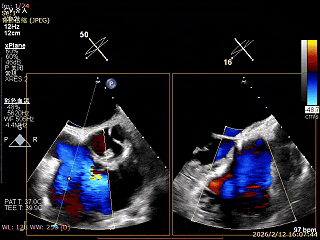

三尖瓣术前评估

三尖瓣反流(重度);肺动脉高压(中度);二尖瓣反流(中度);双房左室增大;左室顺应性减低。

术前食道超声评估

三尖瓣关闭不全重度(4+,平均缩流颈10mm),反流口以前隔、中央为主,部分后隔,瓣叶未见明显脱垂及GAP,三尖瓣环扩张(瓣环平均径43mm),二尖瓣中-重度反流,肺动脉高压(PASP:44mmHg)。

手术效果评估

反流评估:术前4+下降至1+

术前中央反流

术后中央反流

DSA双夹释放后形态无异常,锚定部位均在预期位置,RCA血流未受到影响。

术前瓣环面积

术后瓣环面积

后复查经胸心脏超声,示肺静脉、肝静脉逆流消失,二尖瓣及三尖瓣反流降低至轻度,手术效果良好。